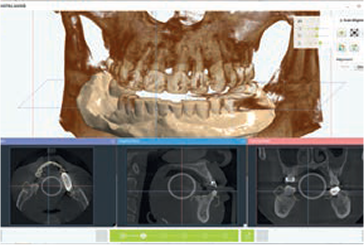

ICP (Iterative Closest Point)

Manual Control

Align 3D Model & CT

Fixture Simulation